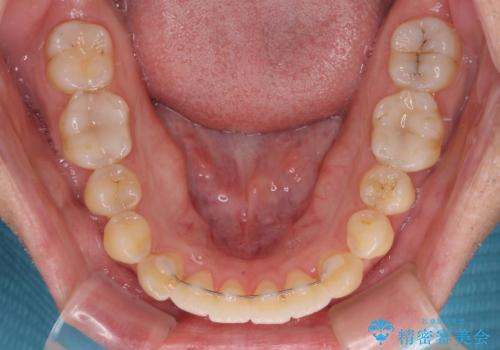

開咬とデコボコを整える インビザライン矯正治療

- 前歯の開咬と叢生を気にして来院された患者様です。

開咬の治療は、前歯を閉じるように動かすとともに、上下臼歯を圧下(骨内にめり込ませる)させることで進めて行きます。

インビザラインは臼歯の圧下を効果的に行えるため、インビザラインを用いて矯正治療を行うこととしました。また、アンカースクリューを用いて、口元の突出感の改善を図りました。